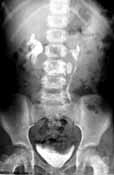

IVU

(intravenous urography)

In this, a dye is injected intravenously and x-ray pictures of the kidneys,

ureters and bladder are obtained. The dye is radio-opaque and seen well with

x-rays. Overnight fasting and good preparation of the colon with Dulcolax are

required. The cost is between Rs 1000 to 2500.